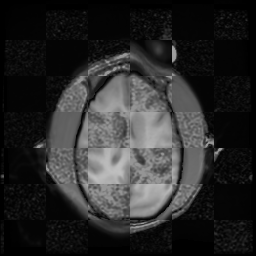

For each of the 10 subjects, we show checkerboard slices in each direction (1) before registration, first row; (2) after rigid->scaleversor->affine registration, second row; and (3) after BSpline registration, third row.

Gucci